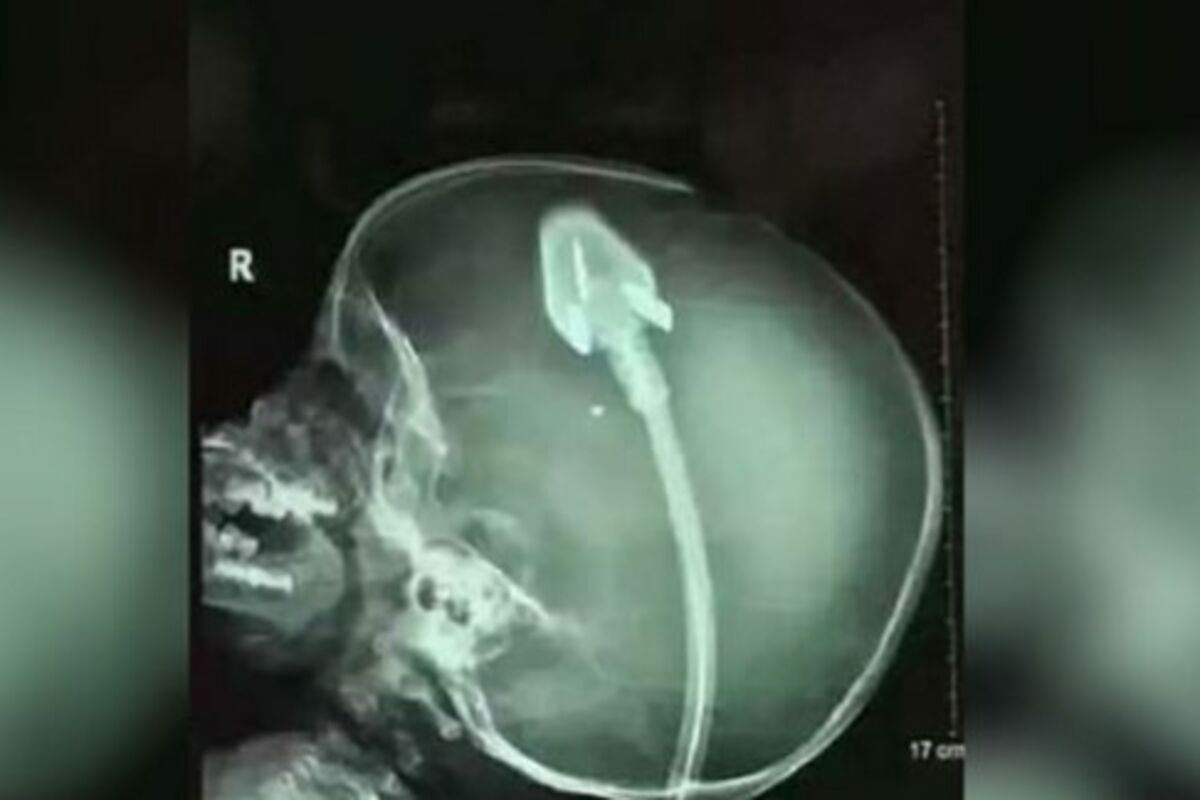

Naime dečak se igrao, kada je pao i udario glavom o utikač za struju. Odmah je prevezen u bolnicu gde je operisan, a rendgenski snimci njegovee glave obišli su svet.